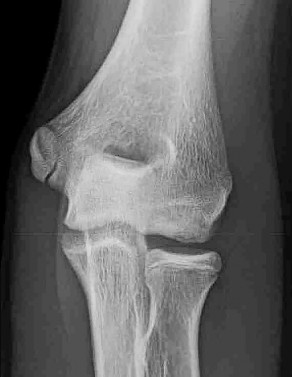

A 5-year-old boy presents with an extension-type Gartland III supracondylar humerus fracture after a fall.

On examination, his hand is well-perfused (pink) with brisk capillary refill, but the radial pulse is absent. What is the most appropriate initial management?